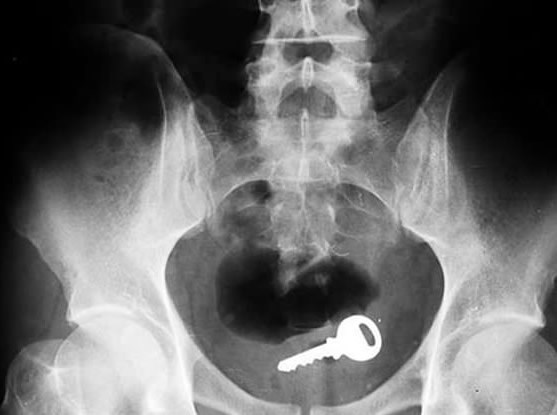

Kad pravi majstor zagubi ključeve